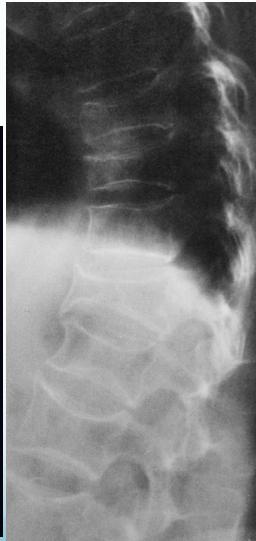

The changes of osteoporosis are best seen in the spine (Lateral thoracic and lumbar spine x-ray )

X-ray lumbar spine (lateral view) of a patient with osteoporosis

The vertebrae have a low-density appearance as a result of the loss of trabecular bone, and the cortical outline of each vertebra appears accentuated.Z

Other potential findings on a spine radiograph in osteoporosis include an abnormal trabecular pattern and biconcave or compressed vertebral configuration.